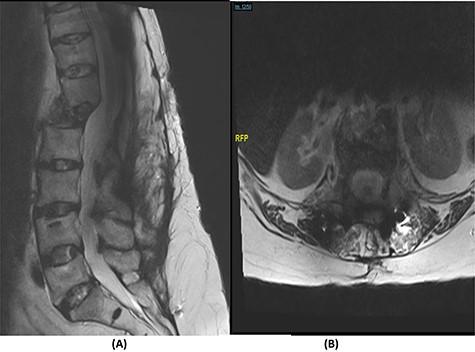

The bridging technique was used to achieve relative stability through posterior fixation until the anti-TB medications cleared the vertebral infection and allowed re-ossification of the destructed levels (T11–L3) to occur. An open biopsy was done intraoperatively to reconfirm the diagnosis of spinal TB. The patient started mobilizing early postoperatively and continued to take the anti-TB medications for 18 months (Fig. 4).

(A) AP lumbar spine X-ray demonstrating the bridging technique. (B) Lateral spine X-ray showing the bridging technique sparing the infected area.

The success rate of surgical TB management is high and effective according to a study based on data collected from 582 patients throughout 11 years [8]. Our patient presented with a destructive spinal lesion and underwent posterior spinal decompression and instrumentation of T11–L3. Nevertheless, due to severe destruction, loosening and poor bone quality of the levels T11–L3, along with the multiple medical comorbidities, anterior surgical intervention with a thoracoabdominal approach with resection of all the levels involved would associate with major morbidities and complications. To achieve a balanced construct and to have multiple fixation points, which was needed to overcome the poor bone quality, the fixation was done from T5 down to the pelvis (Fig. 4), spanning the destructed area and utilizing the bridging technique with multiple rod constructs across the T11–L3 region.